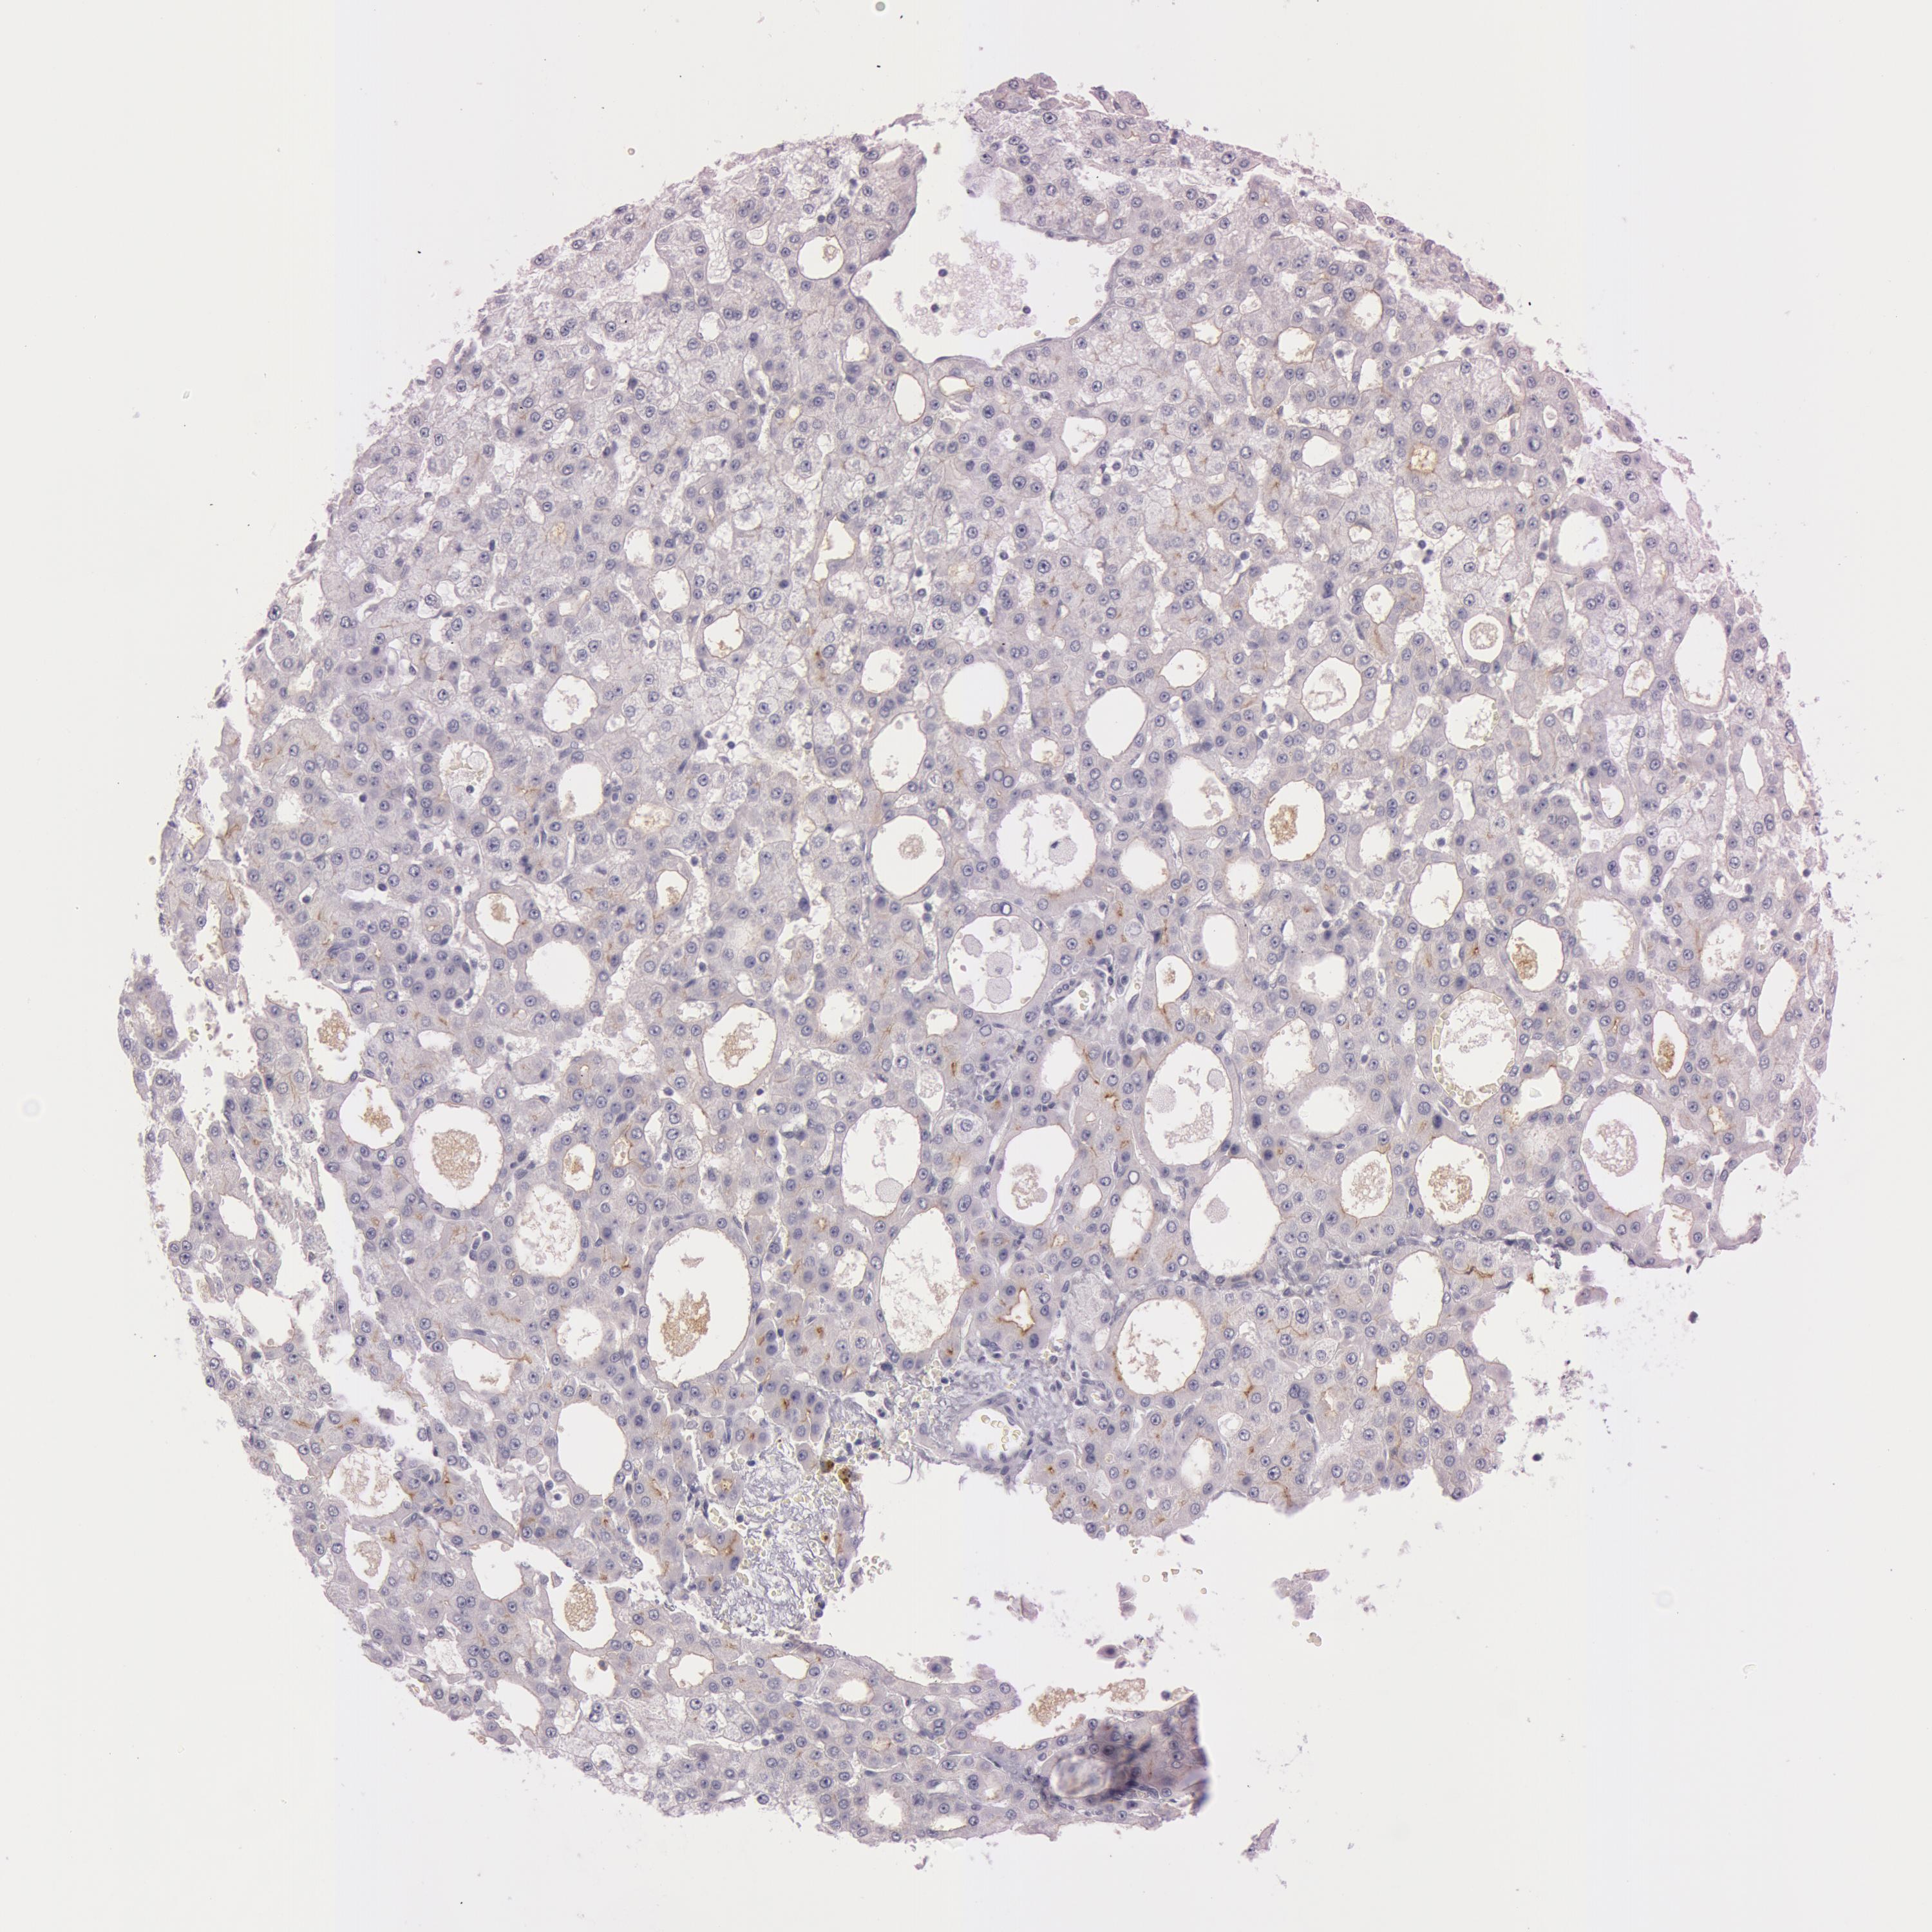

LIVER CANCER - Protein expressioni

A mouse-over function shows sample information and annotation data. Click on an image to view it in a full screen mode. Samples can be filtered based on level of antibody staining by selecting one or several of the following categories: high, medium, low and not detected. The assay and annotation is described here.

Antibody staining in the annotated cell types in the current human tissue is reported as not detected, low, medium, or high, based on conventional immunohistochemistry profiling in selected tissues. This score is based on the combination of the staining intensity and fraction of stained cells.

Each image is clickable and will lead to virtual microscopy that enables deeper exploration of all samples and also displays staining intensity scores, fraction scores and subcellular localization as well as patient and tissue information for each sample.

Antibody CAB001451

Staining

High

Medium

Low

Not detected

Intensity

Strong

Moderate

Weak

Negative

Quantity

>75%

75%-25%

<25%

None

Location

Nuclear

Cytoplasmic/membranous

Cytoplasmic/membranous,nuclear

Cholangiocarcinoma

Carcinoma, Hepatocellular, NOS